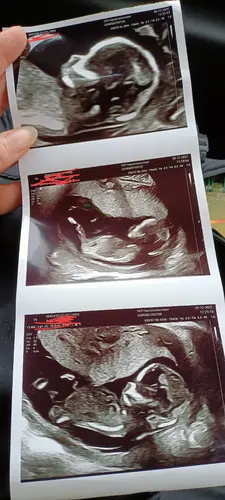

Wat zouden jullie hier bij zeggen?

Jongen lijkt het